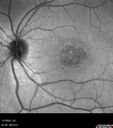

24 year old female She has worn glasses since she was a kid. Since she became an adult her vision started to deteriorate more rapidly. This seems to have been happening since she entered the accounting department for the last two years. Her vision is worse in the light especially when she is driving. She can see green lights in the night but not in the day. She sees better on a dark background than on a light background.

Her mother and father both have inherited retinal diseases. His mother was diagnosed 23 years ago with Stargardts genetically confirmed in Boston. The father has Retinitis Pigmentosa. The mother has seven brothers and sisters and four have Stargardts and they are legally blind. Also one cousin has it.

PMHx benign, Meds: vitamins.

VA OD: Dcc20/160

VA OS: Dcc20/160

IOP: TP: OD:20 OS:21